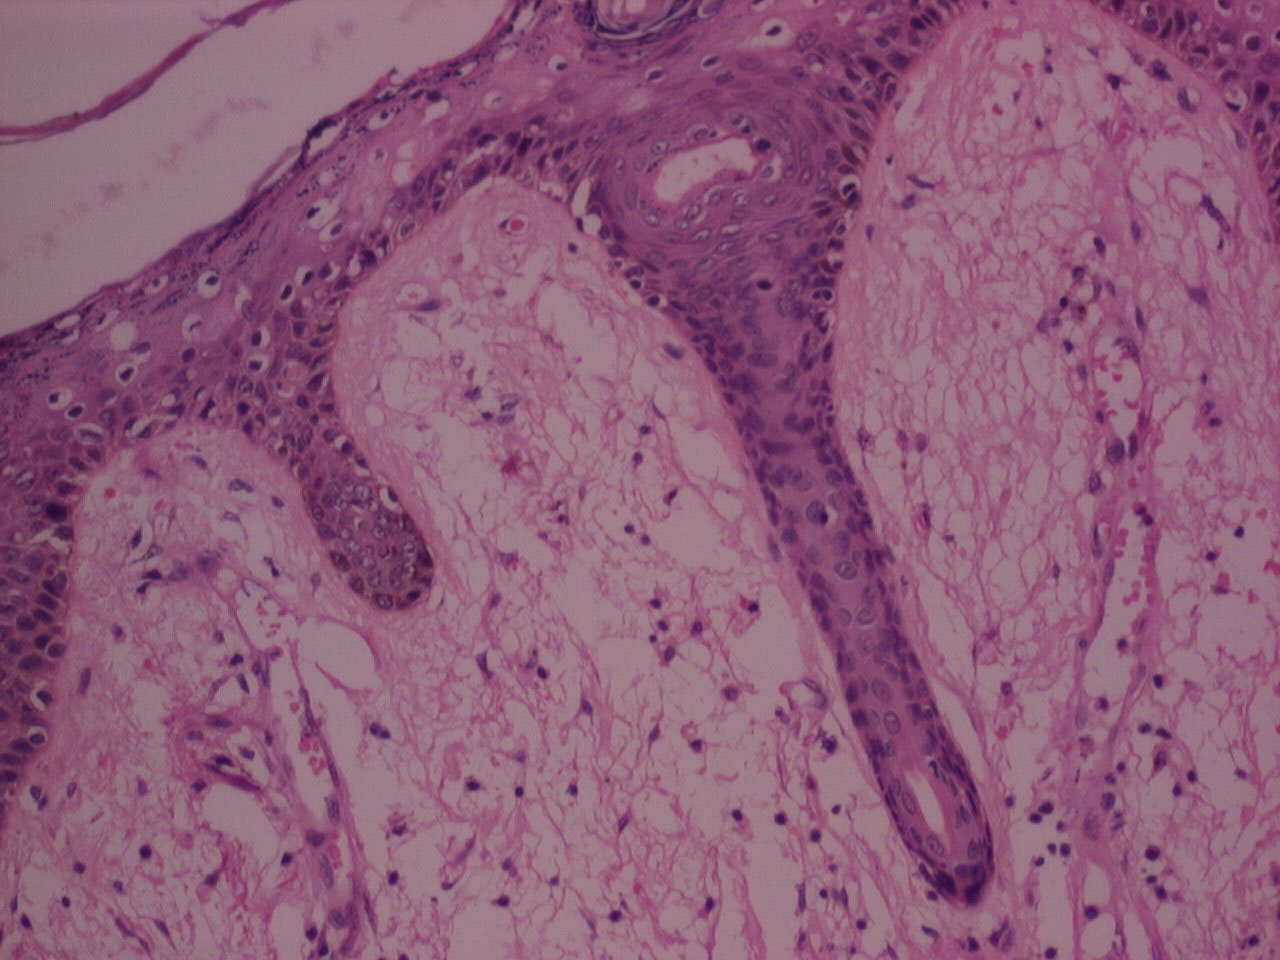

Mann-Whitney U Test displayed p value (> 0.05) , that was statistically not significant, for all criteria's indicating comparable clarity, uniformity, cell morphology, section quality, crispness, nuclear cytoplasmic contrast, nuclear staining, cytoplasmic staining and IHC staining between n-Heptane and xylene (Figure 1, Figure 2, Figure 3, and Figure 4).

Figure 1: H&E stained photomicrograph of section processed with n-Heptane, 10x. View Figure 1

The majority of the samples processed with n-Heptane showed weak to moderate IHC staining for cytokeratin and vimentin (Figure 5, Figure 6, Figure 7, Figure 8 and Figure 9) with none of the sections devoid of staining.

We found no statistical differences in the clarity, uniformity, crispness, section quality between n-Heptane and xylene. Cellular parameters of nuclear & cytoplasmic staining, nuclear cytoplasmic contrast and cell morphology too were comparable between n-Heptane and xylene. The paraffin blocks prepared by using n-Heptane as a clearing agent were easily cut into 4 μm serial sections and ribbon formation was good. No sign of cell shrinkage and deformation in n-Heptane treated sections was observed. In our study 20% of samples processed with n-Heptane showed strong IHC staining for cytokeratin as compared to xylene where 80% of the samples showed weak to moderate IHC staining.